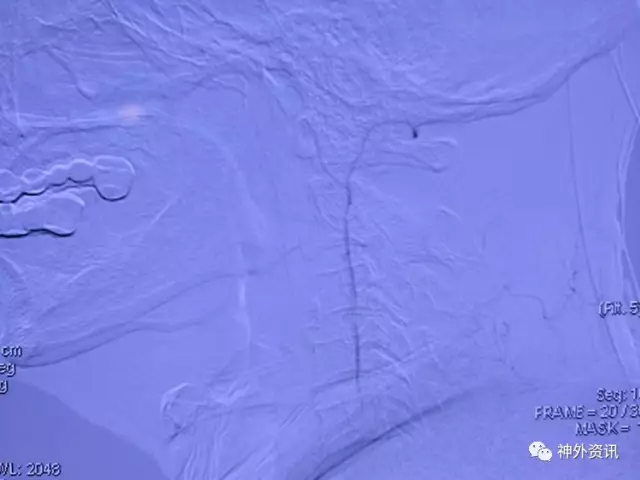

L一VA开口重度狭窄

L-VA正侧位:颅内段各血管显影尚好,左侧PⅠCA供血双侧

R一VA正位:该侧血管管径较粗,应为优势侧,然而同侧PICA/AICA显影不好,头晕原因仍未知道

L一VA开口支架成形满意,术后病人症状缓解

正位造影看不到左ⅤA,开口段内膜过度增生闭了

L-VA晚间可见肌支吻合与VA相通,闭塞节段限于开口段,可否一试把支架与增生内膜斑块取了再通呢?

既然DSA提示L一VA远端肌支吻合血管供血有显影,病人有确切临床症状,这个病人有指征也有再通的可能。

复合手术室一期造影,VA开口通畅,远端血管呈低灌性狭窄

L-VA颅内正侧位造影示pⅠCA显影好,正位示供血双侧,看来病人头晕的缺血症状该结束了